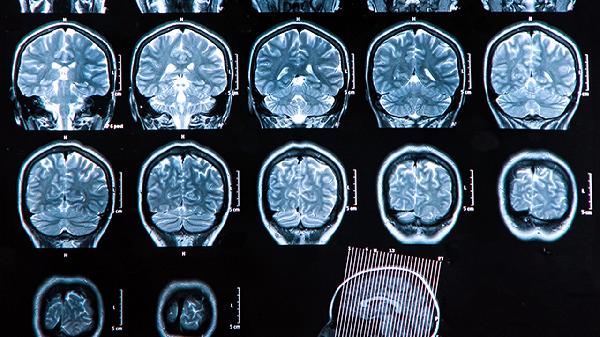

医保报销通常限定于脑血栓形成急性期及恢复期的对症治疗,超出说明书适应症使用可能无法报销。用药需提供明确的脑梗死、脑栓塞等诊断依据,且处方剂量应符合临床诊疗规范。部分地区要求提供影像学检查报告等佐证材料。